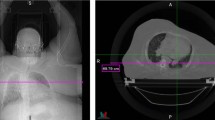

Generative Adversarial Networks (GANs) have gained significant attention in several computer vision tasks for generating high-quality synthetic data. Various medical applications including diagnostic imaging and radiation therapy can benefit greatly from synthetic data generation due to data scarcity in the domain. However, medical image data is typically kept in 3D space, and generative models suffer from the curse of dimensionality issues in generating such synthetic data. In this paper, we investigate the potential of GANs for generating connected 3D volumes. We propose an improved version of 3D α-GAN by incorporating various architectural enhancements. On a synthetic dataset of connected 3D spheres and ellipsoids, our model can generate fully connected 3D shapes with similar geometrical characteristics to that of training data. We also show that our 3D GAN model can successfully generate high-quality 3D tumor volumes and associated treatment specifications (e.g., isocenter locations). Similar moment invariants to the training data as well as fully connected 3D shapes confirm that improved 3D α-GAN implicitly learns the training data distribution, and generates realistic-looking samples. The capability of improved 3D α-GAN makes it a valuable source for generating synthetic medical image data that can help future research in this domain.

In this section, we present side-by-side illustrations of the training data and generated samples by improved α-GAN to highlight the model’s performance. Figure 23 and 24 illustrate training samples and most similar generated data samples for 3D connected and tumor volumes. Generated shapes maintain the connectivity of the voxels, but the level of the convexity is slightly reduced compared in the provided sample compared to the training data.

Fig. 25 and 26 illustrate sample training and generated data instances as obtained by improved α-GAN for 3D volumes and tumors filled with subspheres. Generated shapes for the 3D volumes have smaller subspheres and thus, more concentrated isocenters. However, isocenters’ distribution follows a uniform pattern similar to the training data.